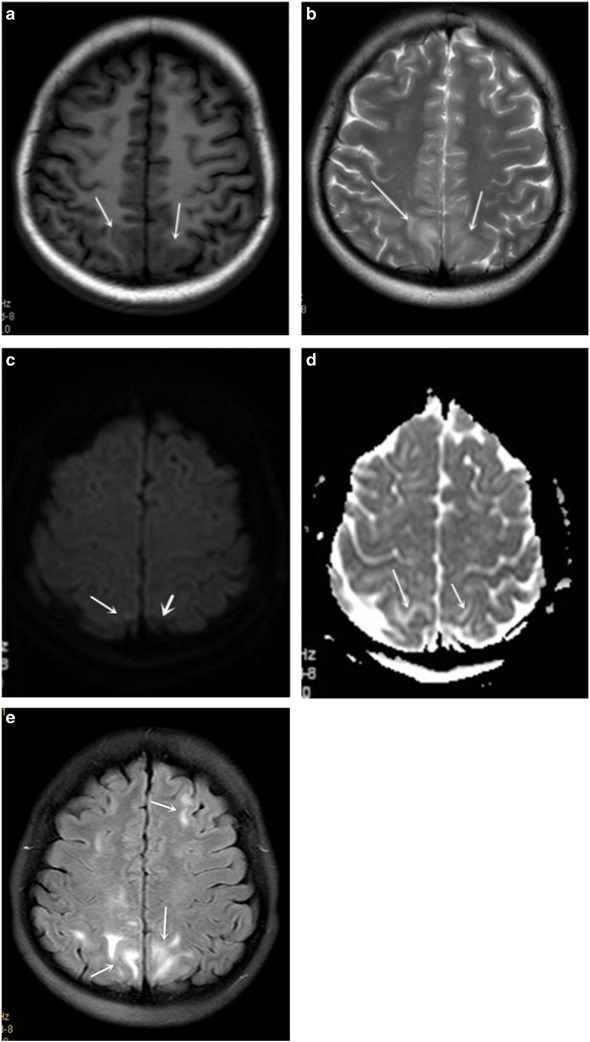

Headache was the most common symptom in RPLS group, whereas visual changes were most frequently observed in the non-RPLS group (71.43% vs. 29.41%). The occurrence rates of headache (P<0.001), visual changes (P=0.045), seizures (P<0.001) and consciousness impairment (P<0.001) were increased in patients with RPLS compared with the non-RPLS group. In addition, dizziness was quite a common symptom for all the patients, and there was no significant difference between the two groups. The imaging features were notable in RPLS patients. For example, T1WI of the MRI exhibited a slightly low signal, while T2WI and FLAIR produced high signals. In addition, the diffusion-weighted imaging sequence exhibited a slightly lower signal, whereas the apparent diffusion coefficient (ADC) exhibited a higher signal that indicated the lesion was vascular edema (Figure 1). For the RPLS patients, the occipital lobe was the most frequently affected area (93.88%), followed by the parietal lobe (65.31%), basal ganglia (32.65%), temporal lobe (30.61%), frontal lobe (26.53%), brainstem (8.16%) and cerebellum (6.12%, Table 2).

(a) MRI on axial T1WI showing low signal predominantly in the occipital lobes, while (b) Axial T2WI showing hyperintensive signal. (c) MRI on axial DWI demonstrates both hyperintensive signal (small arrow) and low signal (thick arrow), while (d) Axial ADC showing hyperintensive signal indicates the lesion was vascular edema. (e) MRI on axial FLAIR showing hyperintensive signal (arrows). ADC, apparent diffusion coefficient; DWI, diffusion-weighted imaging; MRI, magnetic resonance imaging.

Radiology was of great importance to the diagnosis and evaluation of RPLS, and MRI was the gold standard for the diagnosis of RPLS.18 Typically, T1WI of the MRI exhibited a slightly low signal, and T2WI and FLAIR exhibited high signals. In addition, the diffusion-weighted imaging sequence showed a slightly low signal, and apparent diffusion coefficient showed a high signal to distinguish the lesion from vascular edema to cytotoxic edema.13 Typical features include the involvement of the posterior cerebral circulation, indicating bilateral and symmetrical cerebral edema in the subcortical white matter, especially in occipital lobe. However, there were also some uncommon RPLS cases reported, including hemorrhages, infarction and cytotoxic edema.19 The occipital and parietal lobes were the most frequently affected areas in RPLS patients. A recent study indicated the most frequently affected area in RPLS patients with preeclampsia/eclampsia was the occipital lobe (94–98.7%), followed by the frontal lobe (77–78.9%), temporal lobe (64–68%) and cerebellum (53%).20 In our study, the location of RPLS was generally consistent with the literature, although RPLS in the basal ganglia, brainstem and cerebellum was increasingly noted. Possible explanations might include a failure to treat vasogenic edema promptly when it occurred in the first, reversible stage or the continuous increase in blood pressure, which studies have shown to be associated with the involvement of deep brain white matter.21